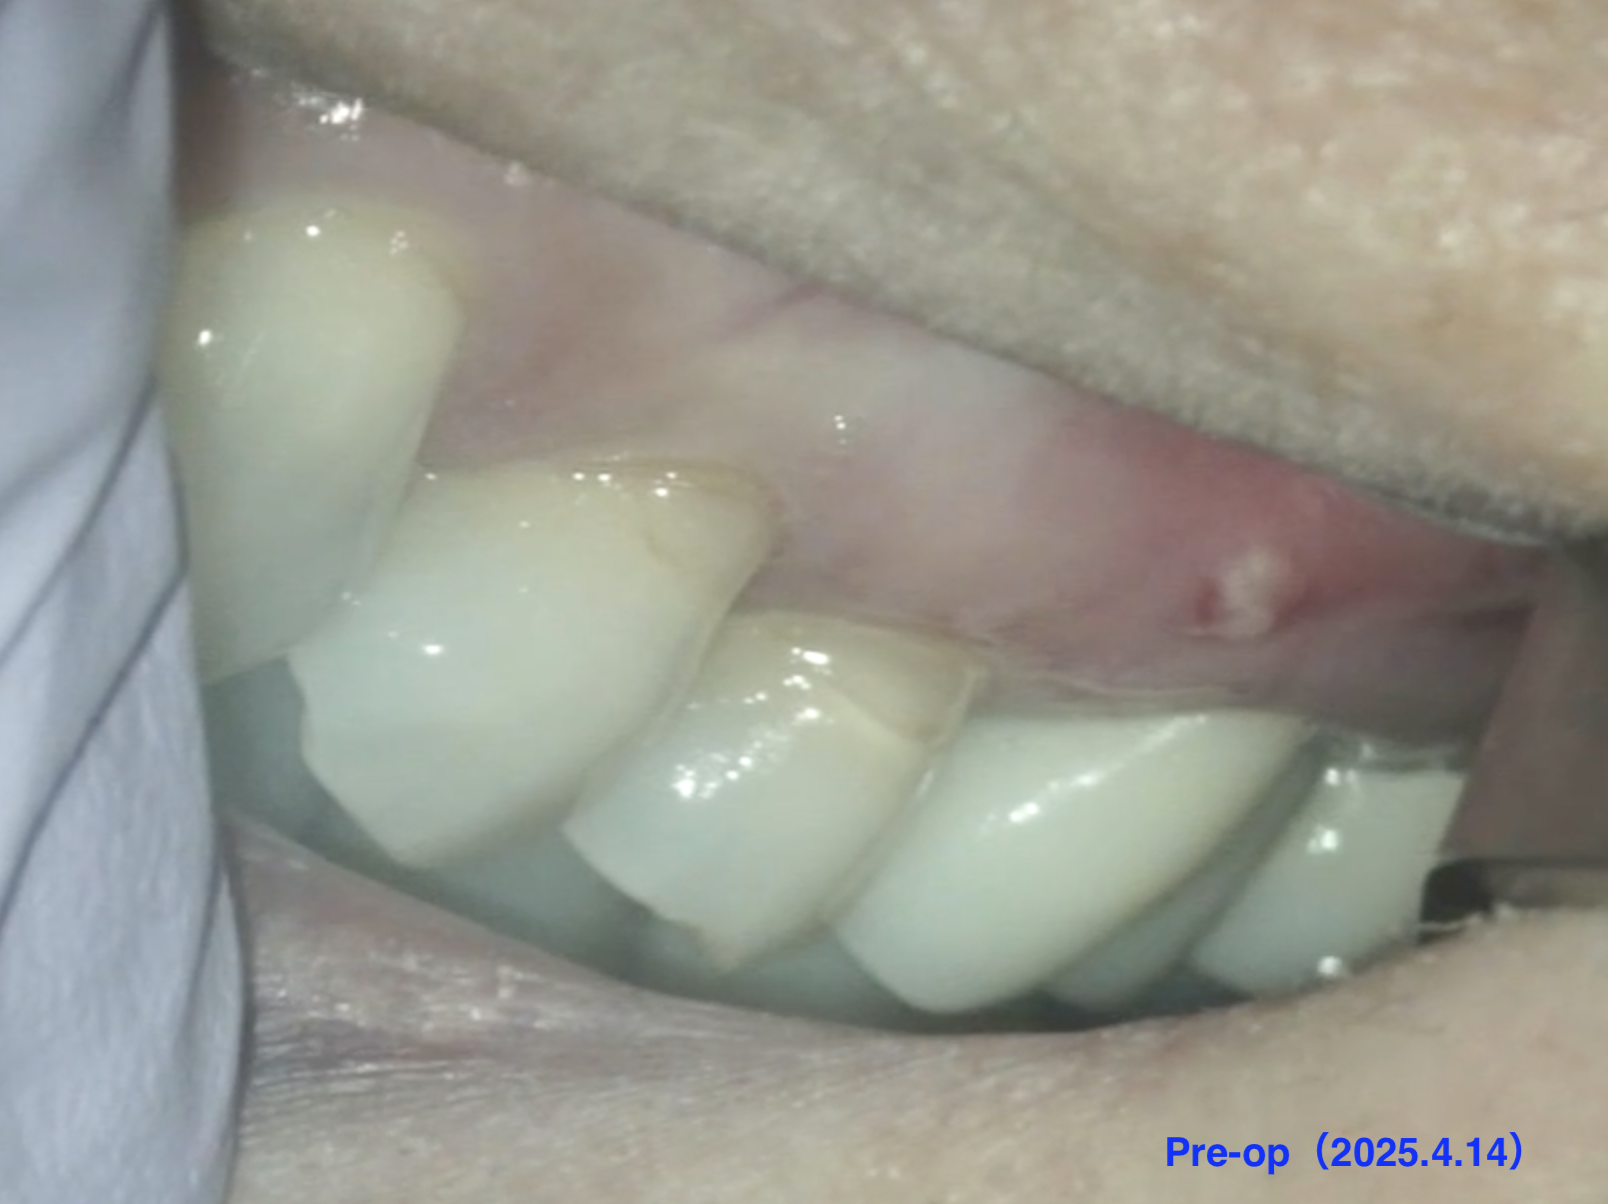

紹介患者さんの治療。

主訴は、

左上奥歯セラミックにした歯が腫れて痛い…セラミックは外したくない。

である。

Pre-op Endo test(2025.4.14)